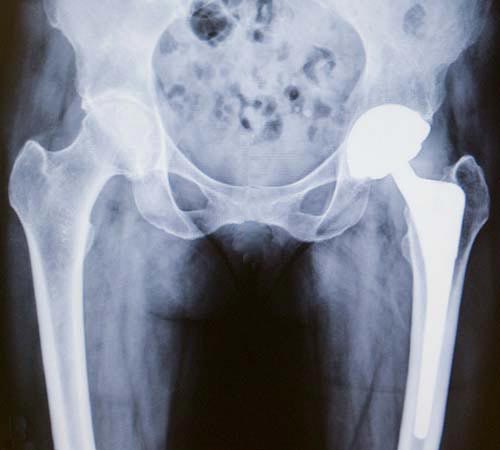

X-ray images of hip revision before and after.